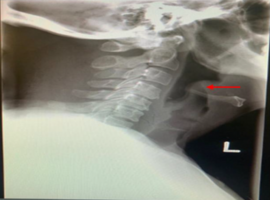

Citation: Koonoolal R, Jurawan J, Fundora RA, Juman S. Endoscopic View of Epiglottitis (An Uncommon Presentation in Adults). Clin Image Case Rep J. 2022; 4(7): 248.